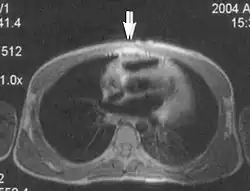

Fig. 3. Metal-related artifacts.[1]

Fig. 4. Metal-related artifacts.[1]

Metal artifacts occur at interfaces of tissues with different magnetic susceptibilities, which cause local magnetic fields to distort the external magnetic field. This distortion changes the precession frequency in the tissue leading to spatial mismapping of information. The degree of distortion depends on the type of metal (stainless steel having a greater distorting effect than titanium alloy), the type of interface (most striking effect at soft tissue-metal interfaces), pulse sequence and imaging parameters. Metal artifacts are caused by external ferromagnetics such as cobalt containing make-up, internal ferromagnetics such as surgical clips, spinal hardware and other orthopaedic devices, and in some cases, metallic objects swallowed by people with pica.[3] Manifestation of these artifacts is variable, including total signal loss, peripheral high signal and image distortion (Figs 3 and 4).[1] Reduction of these artifacts can be attempted by orientating the long axis of an implant or device parallel to the long axis of the external magnetic field, possible with mobile extremity imaging and an open magnet. Further methods used are choosing the appropriate frequency encoding direction, since metal artifacts are most pronounced in this direction, using smaller voxel sizes, fast imaging sequences, increased readout bandwidth and avoiding gradient-echo imaging when metal is present. A technique called MARS (metal artifact reduction sequence) applies an additional gradient, along the slice select gradient at the time the frequency encoding gradient is applied.